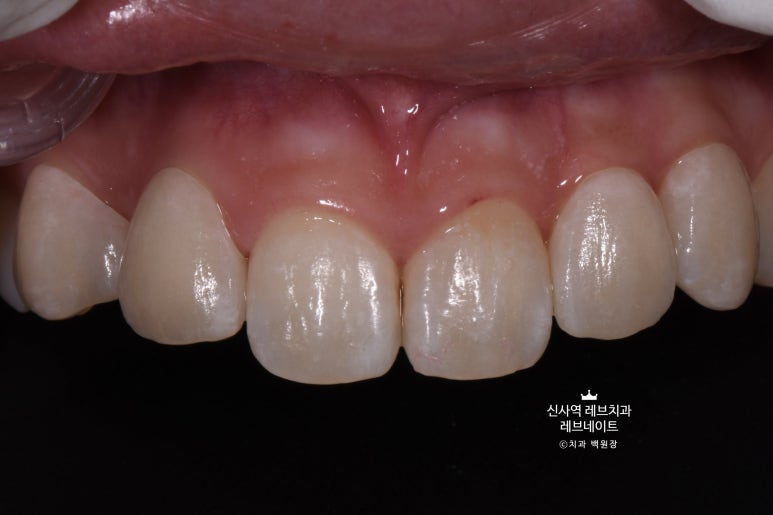

저희 김경호 세라미스트의 솜씨가 돋보이는 사진.

저는 보자마자 감탄을 금치 못했었습니다.

단지 앞면만을 덮는 라미네이트로, 이렇게 정교하게 질감과 색상을 표현할 수 있다니...

더더구나 알록달록이라 표현했던 질감까지도 정밀하게 구현된 것이 기가막히더라구요.

솔직히 어느게 치아고 어느게 레브네이트인지 구별이 안되지 않나요?

다시 봐도 참 신퉁하다는 생각 뿐입니다. ㅎㅎ

이게 진짜 예술작품이구나.. 마스터피스구나~ 하는 생각이 들더라구요.

입 안에서 보면 더 자연스럽습니다.

가로로 길어보이는 치아는 이 정도 웃어서는 보이지 않아요. ㅎㅎ